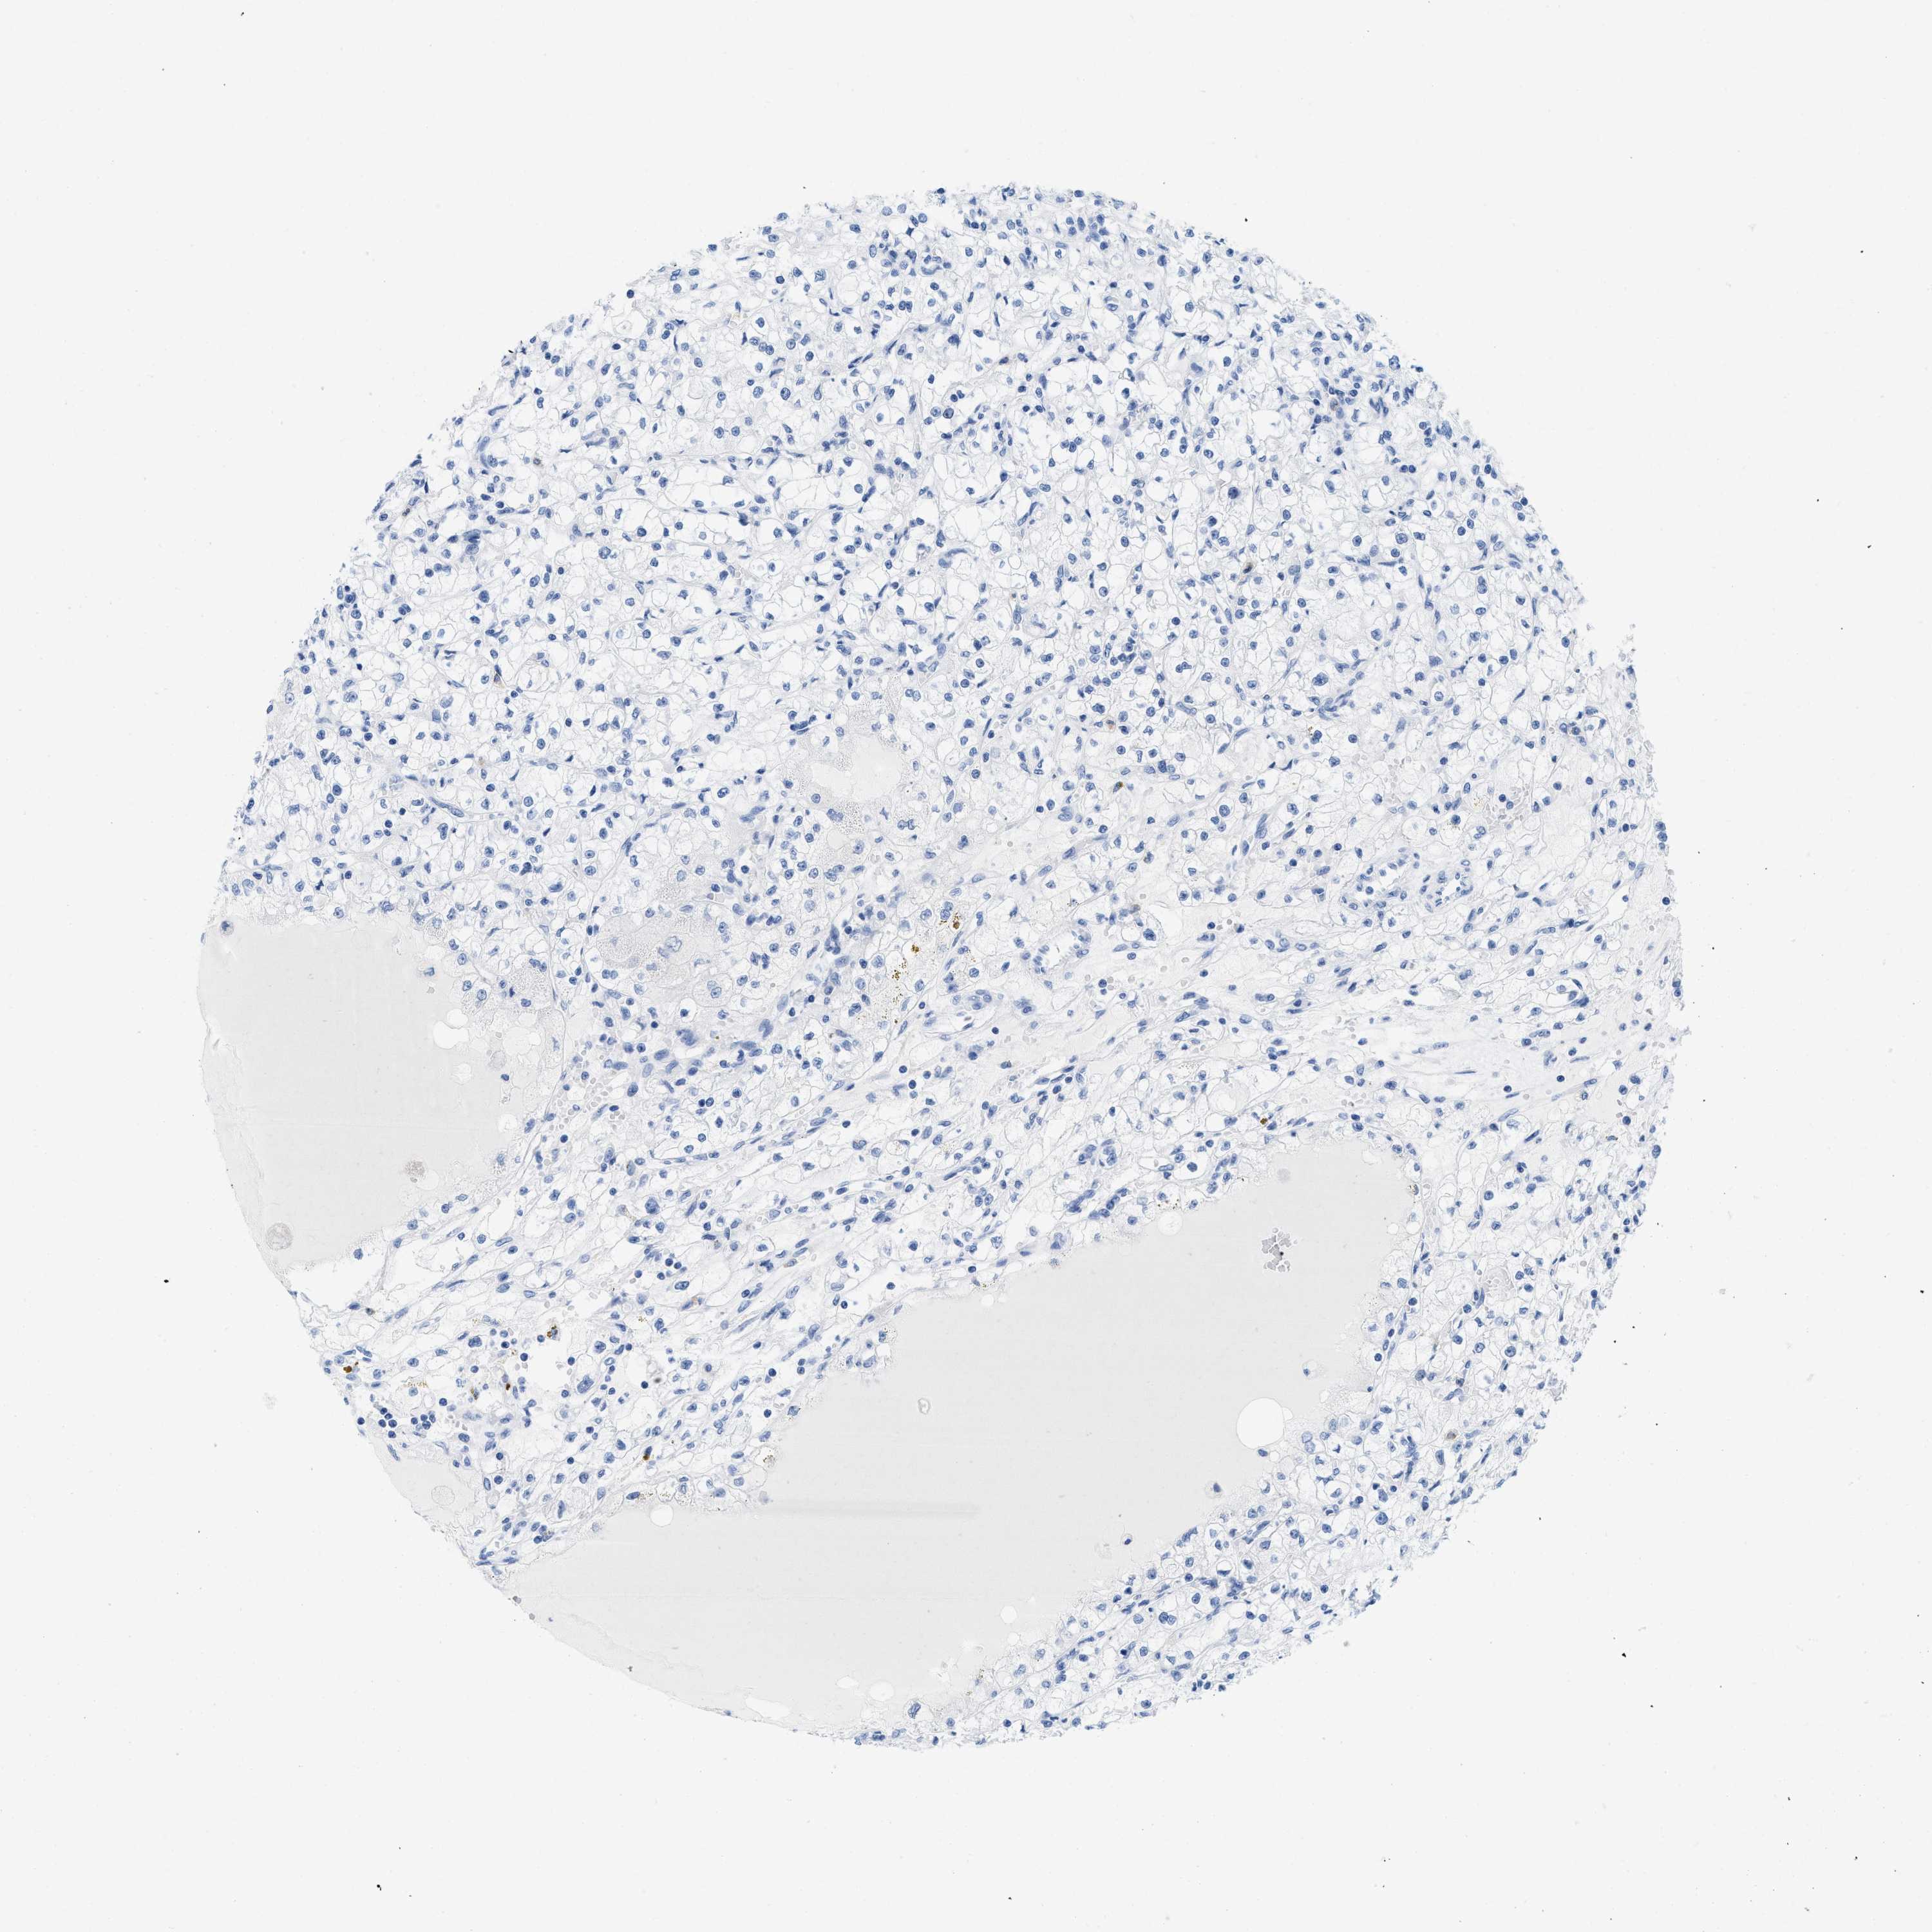

KIDNEY RENAL PAPILLARY CELL CARCINOMA (TCGA) - Interactive survival scatter ploti

The Survival Scatter plot shows the clinical status (i.e. dead or alive) for all individuals in the patient cohort, based on the same data that underlies the corresponding Kaplan-Meier plots. Patients that are alive at last time for follow-up are shown in blue and patients who have died during the study are shown in red.

The x-axis shows the expression levels (FPKM) of the investigated gene in the tumor tissue at the time of diagnosis. The y-axis shows the follow-up time after diagnosis (years). Both axes are complimented with kernel density curves demonstrating the data density over the axes. The top density plot shows the expression levels (FPKM) distribution among dead (red) and alive patients (blue). The right density plot shows the data density of the survived years of dead patients with high and low expression levels respectively, stratified using the cutoff indicated by the vertical dashed line through the Survival Scatter plot. This cutoff is automatically defined based on the FPKM cutoff that minimizes the p-score. The cutoff can be changed by dragging the vertical line or by entering a cutoff value in the square labeled "Current cut-off".

Under the Survival Scatter plot the p-score landscape (black curve; left axis) is shown together with dead median separation (red curve; right axis). Dead median separation is the difference in median mRNA expression between patients who have died with high and low expression, respectively. It is calculated as follows: median FPKM expression of dead patients with high expression - median FPKM expression of dead patients with low expression. This is intended to aid the user in visually exploring custom cutoffs and the associated p-scores and dead median separation.

Individual patient data is displayed and can be filtered by clicking on one or more of the category buttons on the top of the page. Categories describing expression level and patient information include: high, low, alive, dead, female, male and tumor stages. The scale of the x-axis can be toggled between linear and log-scale by clicking on the "x log" button. Mouse-over function shows TCGA ID, patient information and mRNA expression (FPKM) for each patient.

& Survival analysisi

Kaplan-Meier plots summarize results from analysis of correlation between mRNA expression level and patient survival. Patients were divided based on level of expression into one of the two groups "low" (under cut off) or "high" (over cut off). X-axis shows time for survival (years) and y-axis shows the probability of survival, where 1.0 corresponds to 100 percent.

CR1 is not prognostic in Kidney Renal Papillary Cell Carcinoma (TCGA)